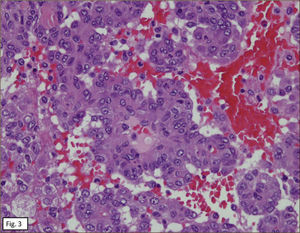

ANATOMÍA PATOLÓGICAEn lóbulo superior derecho se aprecia tumor subpleural bien delimitado, al corte, esponjoso, violáceo, con reticulado blanquecino, zonas hemorrágicas y consistencia friable (Figura 1). Al estudio histológico hay patrones sólido, papilar, trabecular, esclerótico y extensas zonas de hemorragia (Figura 2). Destacan dos poblaciones celulares, con elementos centrales pequeños, redondeados y células periféricas, superficiales, cuboides o cilíndricas (Figura 3). Ambos componentes sin atipias, mitosis ni necrosis. En el estudio inmunohistoquímico los dos componentes neoplásicos dieron positividad para antígeno de membrana epitelial (EMA) y factor transcriptor tiroideo (TTF1) (Figura 4). Hubo también positividad para pancitoqueratina (AE1/AE3) en células superficiales. El índice proliferativo (Ki-67) fue de 1%.

El aspecto histológico con sus diversos patrones arquitecturales, los dos componentes celulares y la inmunoreactividad descrita, permitieron formular diagnóstico de hemangioma esclerosante (neumocitoma).